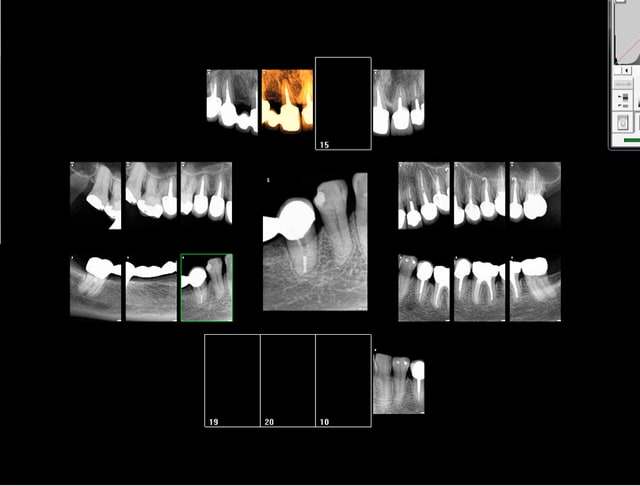

Gné ? De toutes façons un soin seul tu l'as dans l'os. A moins bien sur de le coupler avec un autre acte dans la séance et à ce moment là ton QS te fait gagner du temps. Soit taille empreinte ou pose d'une couronne soit status radio (justifié). Ex en 30 mn et encore j'ai merdé je n'ai pas fait de détartrage.-))))

Capture d e cran 2015 11 16 20.28 - Eugenol

Capture d e cran 2015 11 16 20.29 - Eugenol

Capture d e cran 2015 11 16 20.33 - Eugenol